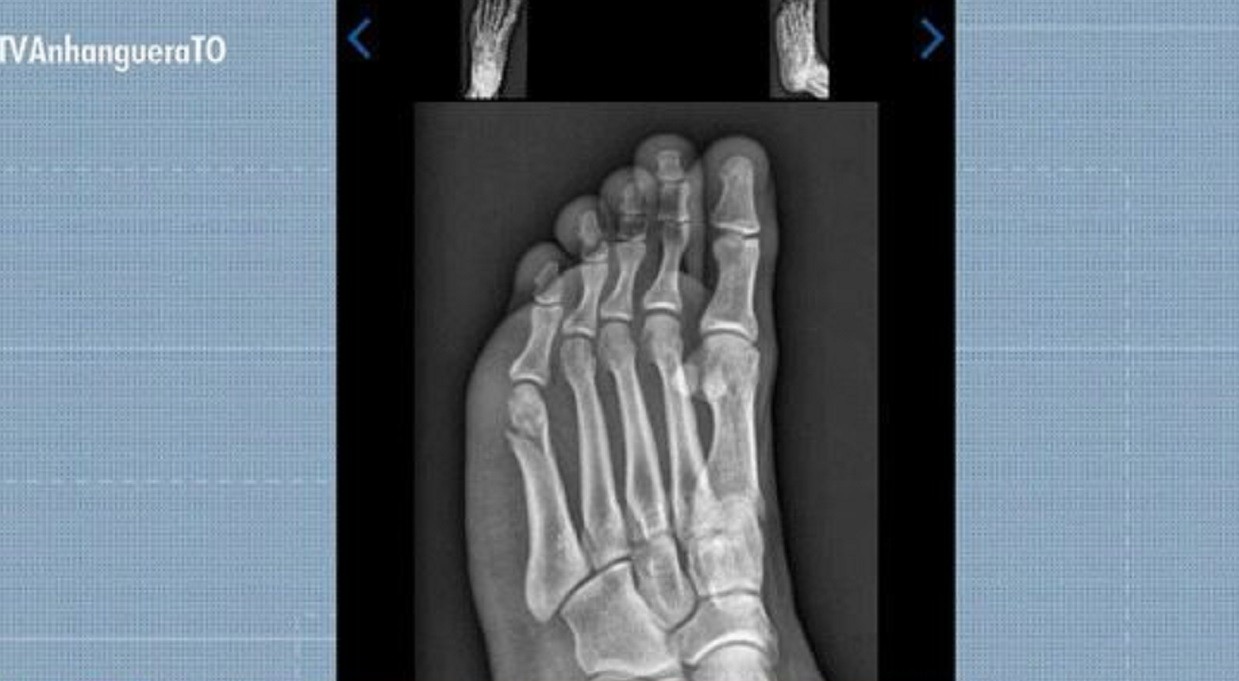

Gabriel Santos Rodrigues foi aprovado no TAF da PMTO mesmo com fratura no pé

Reprodução/TV Anhanguera

Concurseiro concluiu prova de corrida do TAF com fratura no pé